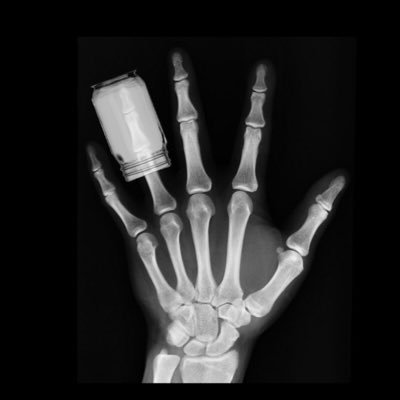

They won't give it to their own children but will absolutely expect you to give to yours.